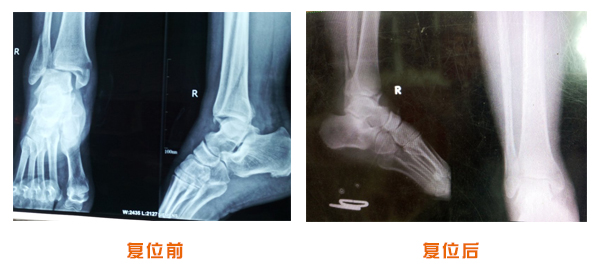

踝關節脫位骨折治療前后對比